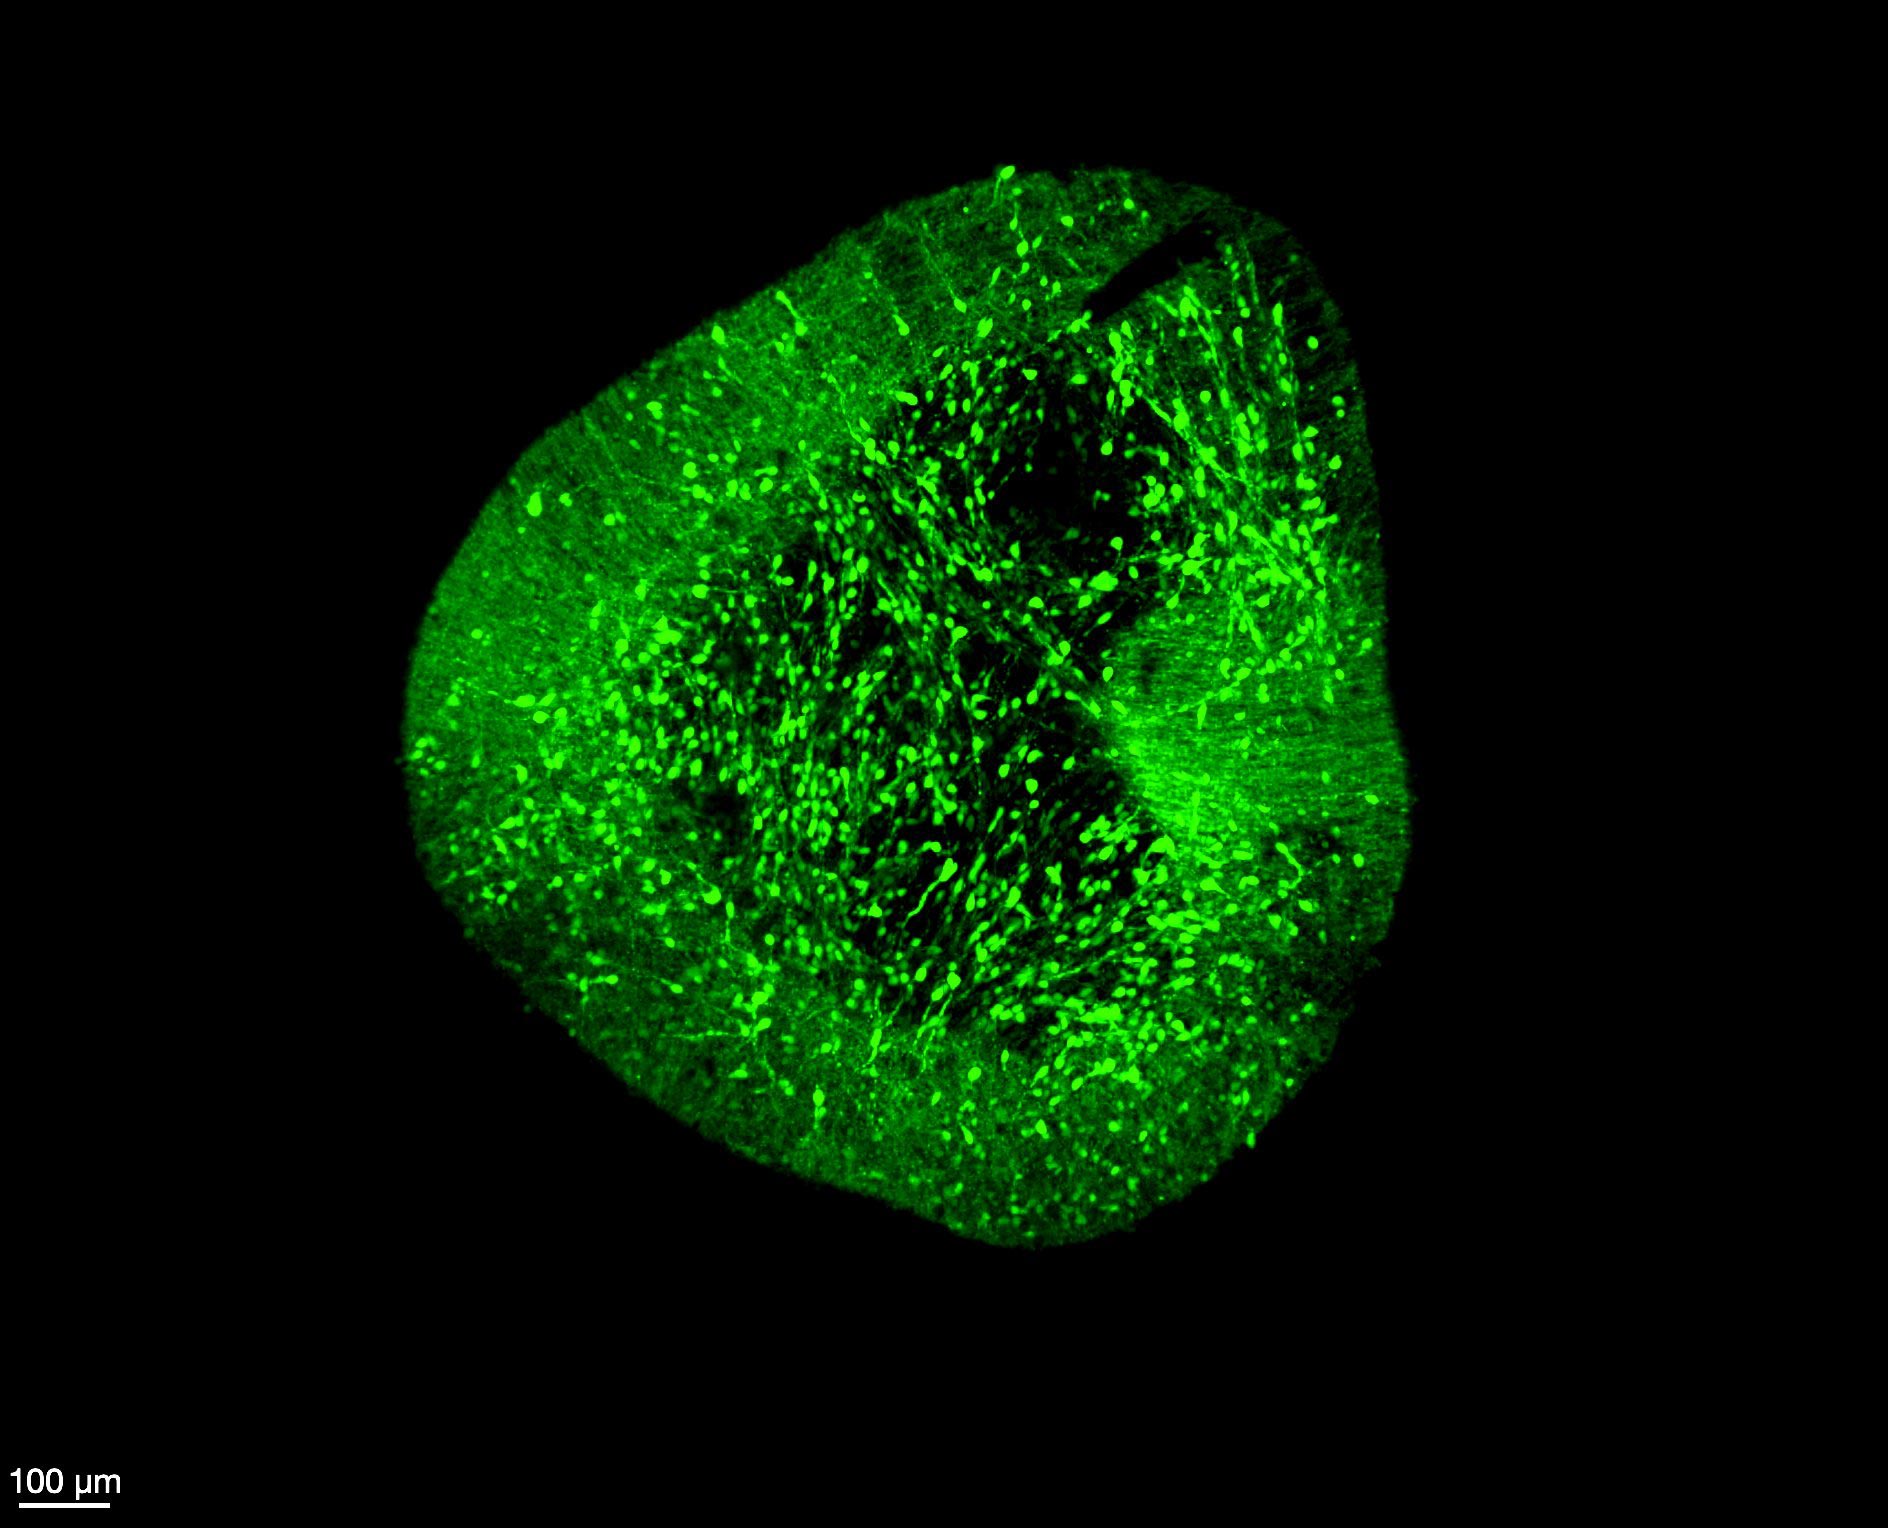

More younger adults in Singapore developing glaucoma, likely because of untreated myopia